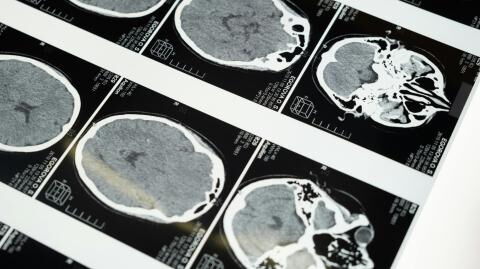

Doctors shocked by inside of his body

SB was pale, his heart rate was worryingly high, and his blood pressure would drop when he stood up. His doctors concluded that he was dealing with haematemesis - that he was bleeding internally and that was the blood he was vomiting.

Indeed, the NHS suggests that ‘some people feel sick, vomit, have abdominal pain or ringing in their ears (tinnitus) after taking too much ibuprofen’. In SB’s case, it had gone on for so long that he had bleeding ulcers in his oesophagus and his stomach and his kidneys were failing.